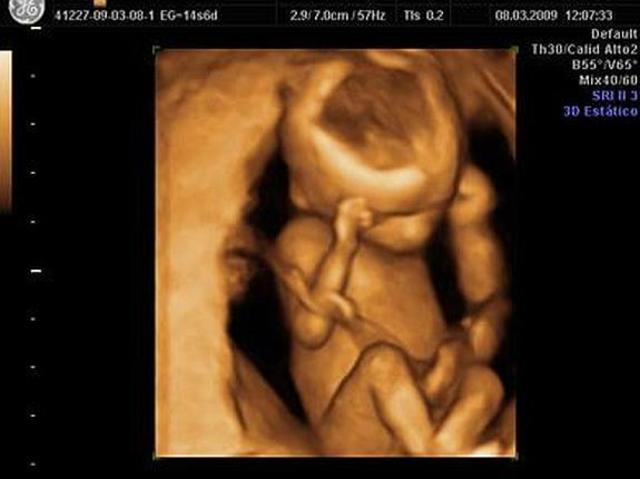

El cerebro es altamente complejo, y constituye casi la mitad del peso corporal de los embriones.

El 75 % de los embriones de muestra ser diestros el resto zurdos , y la otra mitad no muestra ninguna preferencia.

El embrión se vuelve mas activo físicamente.

El embrión hace movimientos de respiración intermitentes, asi no haya aire en el útero.

Los riñones producen orina.

En los varones los testículos comienzan a producir y liberar testosterona.

Su crecimiento corporal se asemeja a un adulto.

• SEMANA 8

SEMANA 8

Crecen cejas y vello al rededor de la boca.

8 Semana marcan el fin del periodo embrionario.

Durante esta etapa el embrión humano se ha desarrollado desde una única célula, hasta casi mil millones.

EL embrión posee el 90% de las estructuras.